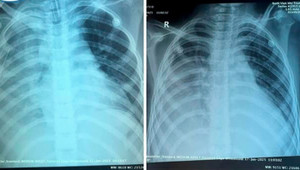

Sau 20 ngày nỗ lực phối hợp giữa các đơn vị, bác sĩ Bệnh viện Nhi Trung ương đã giành lại sự sống cho bệnh nhi Ấn Độ bị viêm phổi hoại tử.